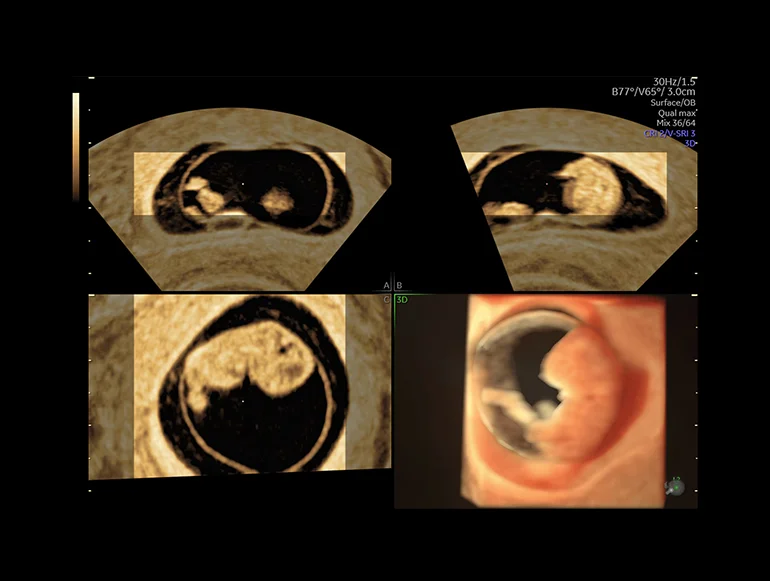

Тазовое дно (серия плоскостей), визуализированное с помощью функции SonoPelvicFloor на основе ИИ

Внутриматочная перегородка, визуализированная с помощью функции Uterine Trace

Точность результатов и сроки имеют решающее значение. Положитесь на систему Voluson Expert 20, которая поможет вам с легкостью найти ответы на важные вопросы. Даже на ранних сроках беременности при визуализации сердца плода или органов таза полный набор наших передовых отраслевых инструментов обеспечивает отличную детализацию изображений, скорость исследования, а также большую гибкость, необходимые для раннего выявления и диагностики, а также для своевременного медицинского вмешательства.

SonoCNS на основе ИИ выравнивает и отображает рекомендуемые проекции и результаты измерений при объемной 3D-визуализации мозга плода, тем самым поддерживая выполнение последовательных измерений и высокую эффективность.